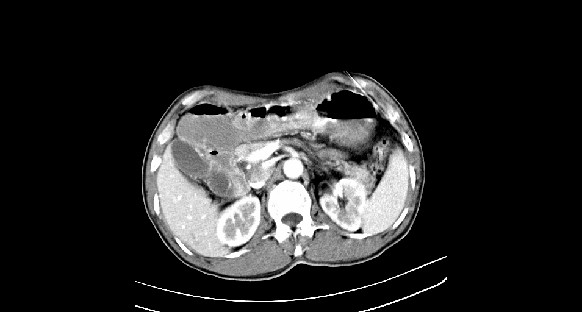

男性,70岁,体检b超发现左肾占位,请各位战友发表一下观点

左肾有两个病灶,且较大的病灶内可见点状钙化灶,增强扫描边缘也是呈渐进性强化,中央部分未见明显强化